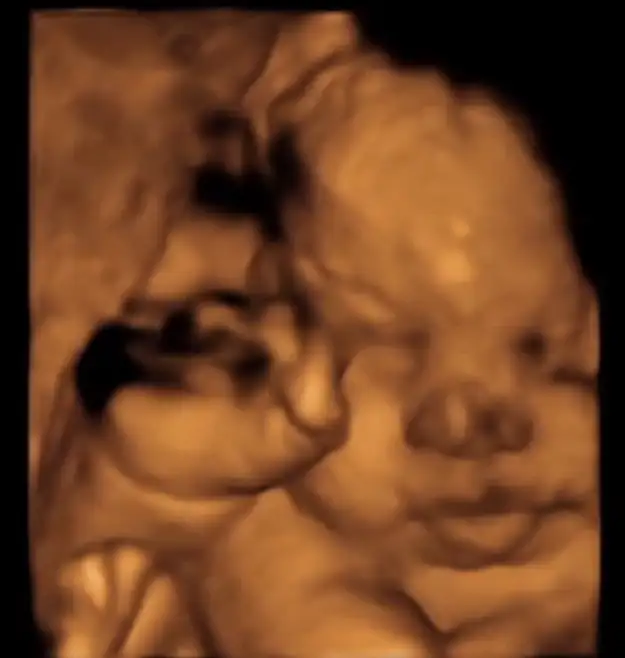

Kızlaarr dün kontrolüm vardı allaha şükür herşey yolunda dün SAT'a göre tam 32+0'dım ama bebek ileride 34+2 ile uyumlu çıkıyor. 2308 kg olmuşuz suyumuz da oldukça iyiymiş :) Doktor 19 Ocaktan sonrasını öngördü :)

Yaa masallah ne guzel pozlar vermis annesii bizimki yuzunu hep plesentaya yasliyor bi eliyle de kalan tarafi kapatiyor 2 aydir sadece yan profilden ayni 1-2 pozu var o kadar bebemin neye benzedigini tam bilmiyorum 🤣🤣 doktor da ugrasiyor baya aman saglikli olsun siz gormeniz gerekeni gorun de biz dogunca goruruz diyorum artik